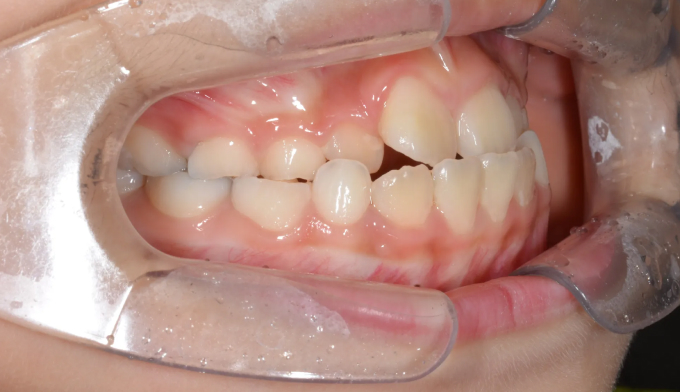

안모상으로는 반대교합도, 주걱턱도 심해보이지 않습니다.

하지만 엑스레이 검사시 주걱턱 경향이 심한 경우로 성장조절을 시작하였습니다.

1차교정 후 영구치가 다 나올때까지 지켜본 결과 1차교정으로 인해 보다 더 자연스러운 안모를 가지게 되었다고 생각합니다. 위턱이 아래턱 안에 갇혀있게 된다면 중안면부위의 결핍이 주걱턱 경향을 더 심하게 만들 가능성이 높기 때문입니다.